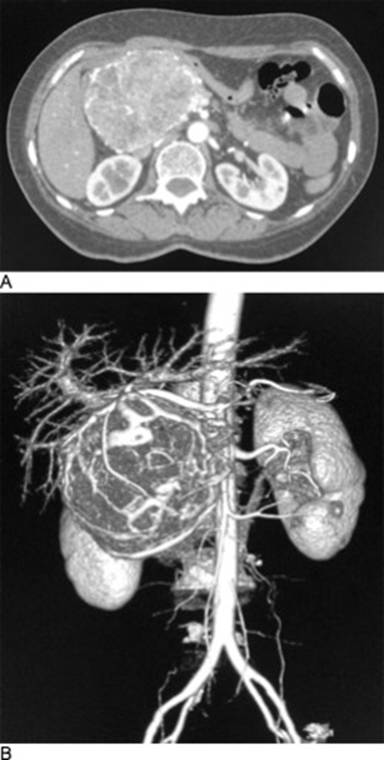

This is a case of a 52-year-old female who was admitted in our Hospital with abdominal pain and epigastric discomfort, findings on the physical examination were palpable mass on right hypocondrium and mild tenderness. She did not have history of other comorbidities. The Ultrasonography and CT scan findings were: a well-circumscribed tumor arising from the right hepatic lobe, diameter of 90mm, compressing other abdominal structures, suggesting as a possible diagnostic and hepatic hemangioma (Figure 1). Initial management was CT-guided angioembolization (two sessions). After this management, she presented a mild relief of the symptoms. A new CT scan revealed a mild reduction on tumor´s size; location of the lesion suggested a tumor arising of the head of the pancreas with clear borders, attenuation values of 18-27 Hounsfield units, heterogeneous enhancement and vascularity present within, the adjacent organs were compressed, and no enlarged lymph nodes were found (Figure 2). Laboratory tests, tumor markers (CEA and CA19-9) and gastric endoscopy were normal. Endoscopic ultrasound was not available in our institution. At this scenario, lacking of biopsy, high suspicious of malignancy, the patient´s symptoms and because the tumor´s size, we decided to perform a pylorus preserving pancreaticoduodenectomy; there was a total bleeding of 400ml and surgical time of 5 hours. It was no need for ICU admission and transfusions. No surgical complications were reported. Before discharge of our service, patient presented seizures secondary to arteriovenous malformation in frontal lobe found in brain CT and MRI; she had no previous history of neurologic symptoms. Diagnostic and therapeutic protocol was in charge of Neurology and Neurosurgery department, but she died one month after the surgery. Histopathological findings were: hemolymphangioma of pancreatic head; with a size of 8x6.5x6 cm; solid component with focal mucinous cysts. No invasion to others structures were reported. Peripancreatic lymph nodes were normal (Figure 3).

Figure 1. A. CT scan demonstrates a heterogeneous mass, initially was suspected to be a hepatic hemangioma. B. 3-D reconstruction shows a highly vascularized mass, which is suitable for the head of the pancreas. |